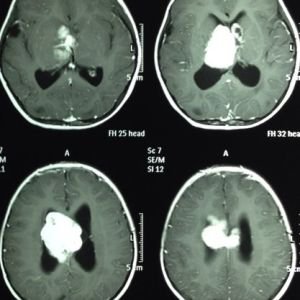

ESCLEROSIS TUBEROSA